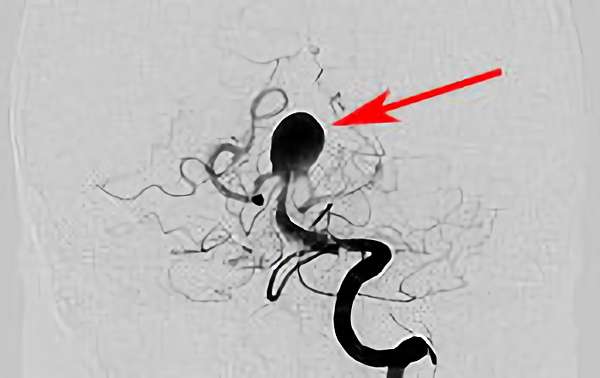

No.1631 手術中